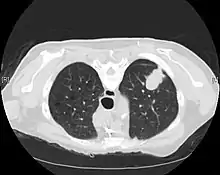

A chest x-ray (radiograph) is often the first imaging test performed when a person presents with cough or chest pain, particularly in the primary care setting. A chest radiograph may detect a lung nodule/mass that is suggestive of cancer, although sensitivity and specificity are limited.

CT imaging provides better evaluation of the lungs, with higher sensitivity and specificity for lung cancer compared to chest radiograph (although still significant false positive rate[27]). Computed tomography (CT) that is specifically aimed at evaluating lung cancer includes the chest and the upper abdomen. This allows for evaluation of other relevant anatomic structures such as nearby lymph nodes, adrenal glands, liver, and bones which may show evidence of metastatic spread of disease.[4] Indeed, the US Preventative Services Task Force recommends annual screening with low-dose CT in adults aged 55 to 80 years who have a 30 pack-year smoking history and currently smoke or have quit within the past 15 years, with certain caveats (see Lung cancer screening).[28]

Nuclear medicine imaging, such as PET/CT and bone scan, may also be helpful to diagnose and detect metastatic disease elsewhere in the body.[7] PET/CT uses a metabolically active tracer that allows clinicians to identify areas of the body that are hypermetabolic. Increased uptake of the tracer occurs in malignant cells and areas of inflammation or infection. Integrating the imaging reflective of metabolic activity with normal CT imaging allows for higher sensitivity and specificity compared to PET alone.[4]

MRI is reserved for patients with advanced disease where intracranial, or brain, involvement is likely. It is also helpful for evaluating the extent of chest wall, diaphragmatic, brachial plexus (such as in the case of superior sulcus tumors), or spine involvement.[4]